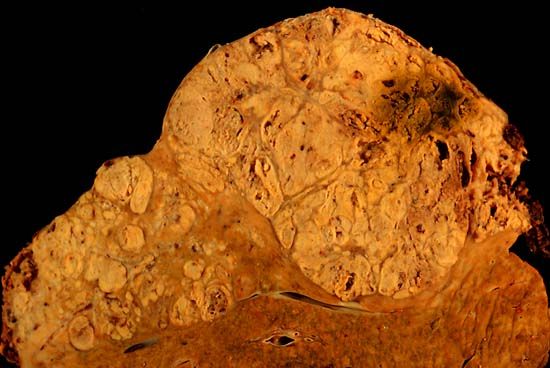

Photo caption: A section from a formalin-fixed specimen taken from an individual who died shows hepatocellular carcinoma occupying much of the volume of a cirrhotic liver. (Public domain image)